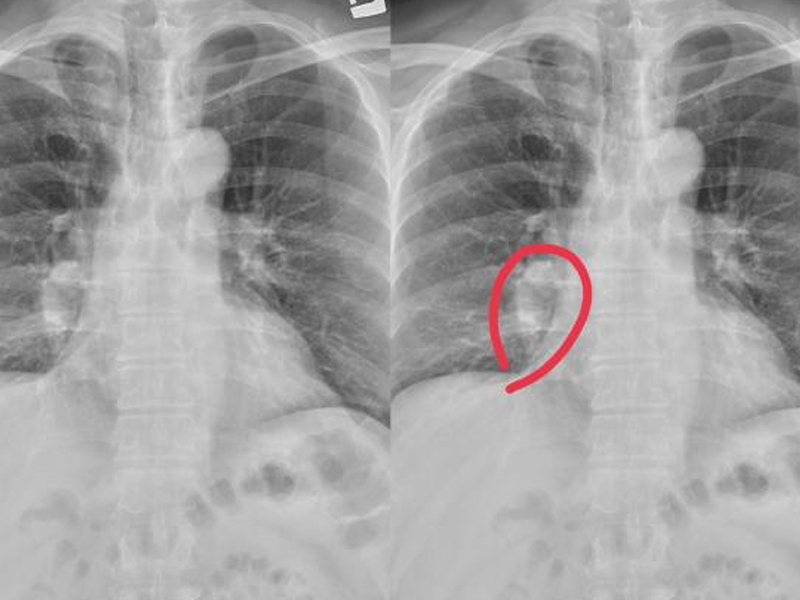

肺癌仍然是發病率和死亡率最高的惡性腫瘤,尤其是男性。具體病因不是很清楚,一般認為是遺傳的,吸煙或觸摸二手煙和油煙、環境、心理因素和其他相關因素。提到肺癌,人們必定會想到乾咳、咳血、胸悶、呼吸短促等,但並非所有肺癌患者都會呈現這種症狀,這可能表現為雙腿。假如你的腿有以下症狀,你需求儘快去醫院做低劑量的胸部螺旋 CT 篩查肺癌。

1. 雙腿皮膚反常

中醫說:肺主要是皮毛,所以你能夠通過皮膚狀況來判斷肺功用是否傑出。肺是氣體交換的重要器官,但也能運送氧氣。在肺功用正常的前提下,血液中有滿足的氧氣。但在肺癌變後,必然會影響肺功用,使腿部缺氧,導致腿部皮膚白色或紫色。

2. 長痣

腿上的痣問題不大,但短時間內增長敏捷,尤其是直徑大於 2cm 時,伴有痣破裂、膿液、邊界不清,需求高度懷疑肺癌。

3. 腿部浮腫

長期坐着或站着.喝太多的水很容易導致腿部水腫,但只要積極的改進能夠緩解。假如腿部繼續水腫,按壓後反彈速度較慢,首先排除腎病,但也需求警惕肺癌。因為癌細胞的快速增殖速度,它能夠耗費體內的大部分能量,這很容易導致細胞浸透壓力失衡,使水逐漸浸透到細胞組織中。隨着癌細胞的擴散,它能夠壓榨下肢血管或神經,然後導致繼續的水腫,肺癌越嚴峻,水腫問題就越顯着。

4. 關節痛苦

許多肺癌患者在發病期間會呈現難以忍受的腿部痛苦,尤其是在行走時。因為癌細胞在增殖過程中能夠吸收肺部養分,也能夠轉移到其他部位。骨骼和關節首戰之地,因為骨骼中有豐富的血液和促進癌細胞生長的因素。